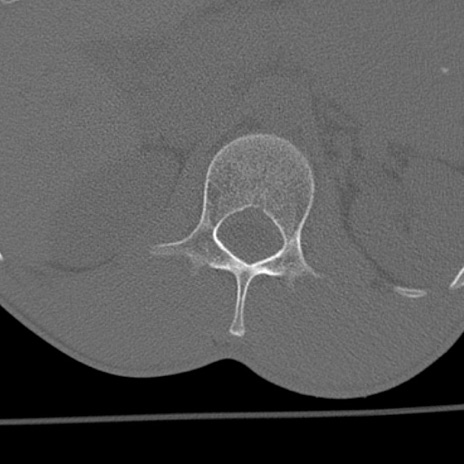

症例3 腰椎CT(横断像)

腰椎CT